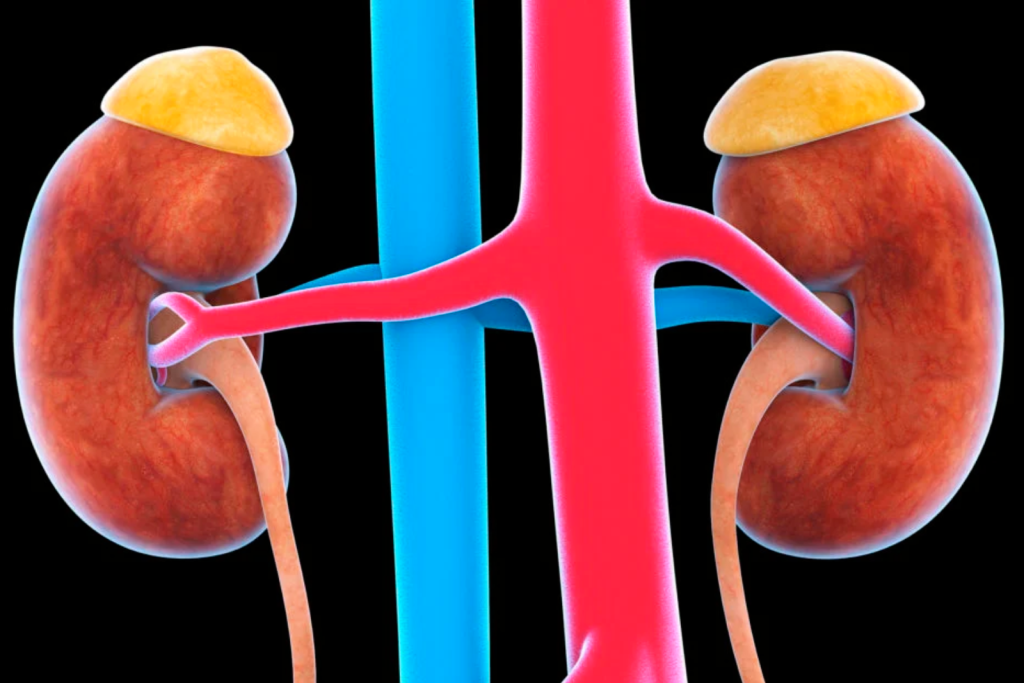

Adrenal tumor

Adrenal insufficiency

Adrenal disorders